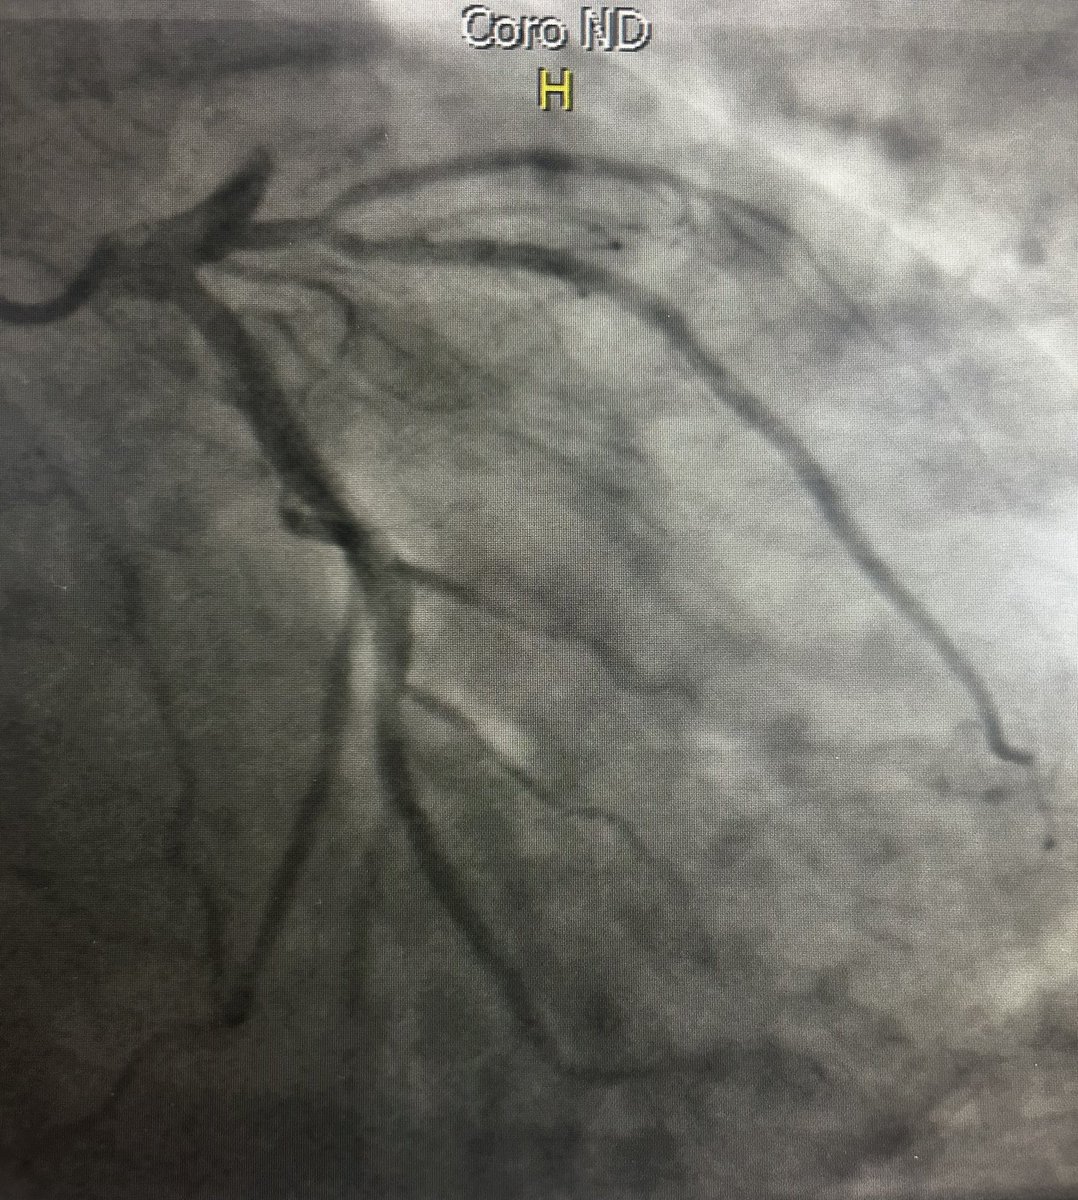

How often have you encountered simultaneous acute thrombosis of proximal RCA and LAD. 57yo M. Exercises regularly. No risk factors. Sudden onset of chest pain/syncope while motorcycling and at the top of a hill. Thoughts? @torresviera @DrRajeshG1 @mmamas1973 @Hragy @mandeep_mayo